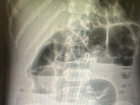

Хирурги извлекли 134 магнитных шарика из живота ребёнка в Волгограде 09.09.2025 Общество -